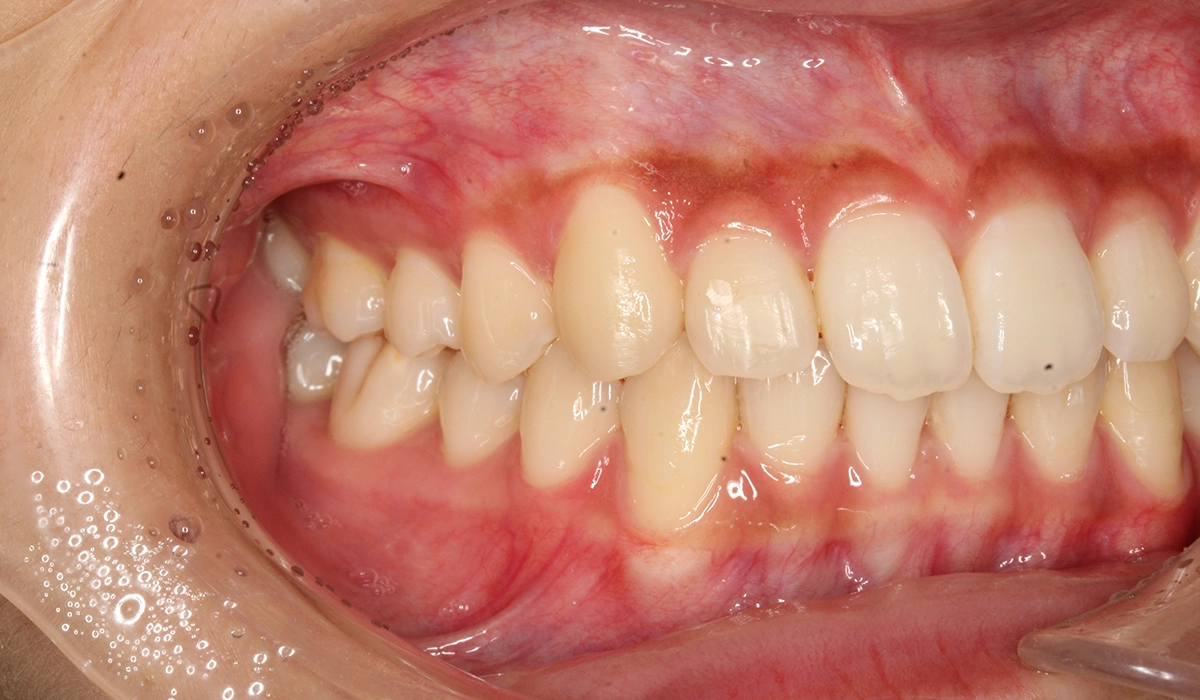

術前:左側

術後:左側